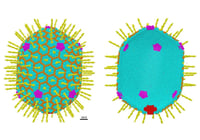

Como virus pero artificial Así funcionan los vectores artificiales que pueden entraren las células humanas para realizar tareas específicas como la edición génica…